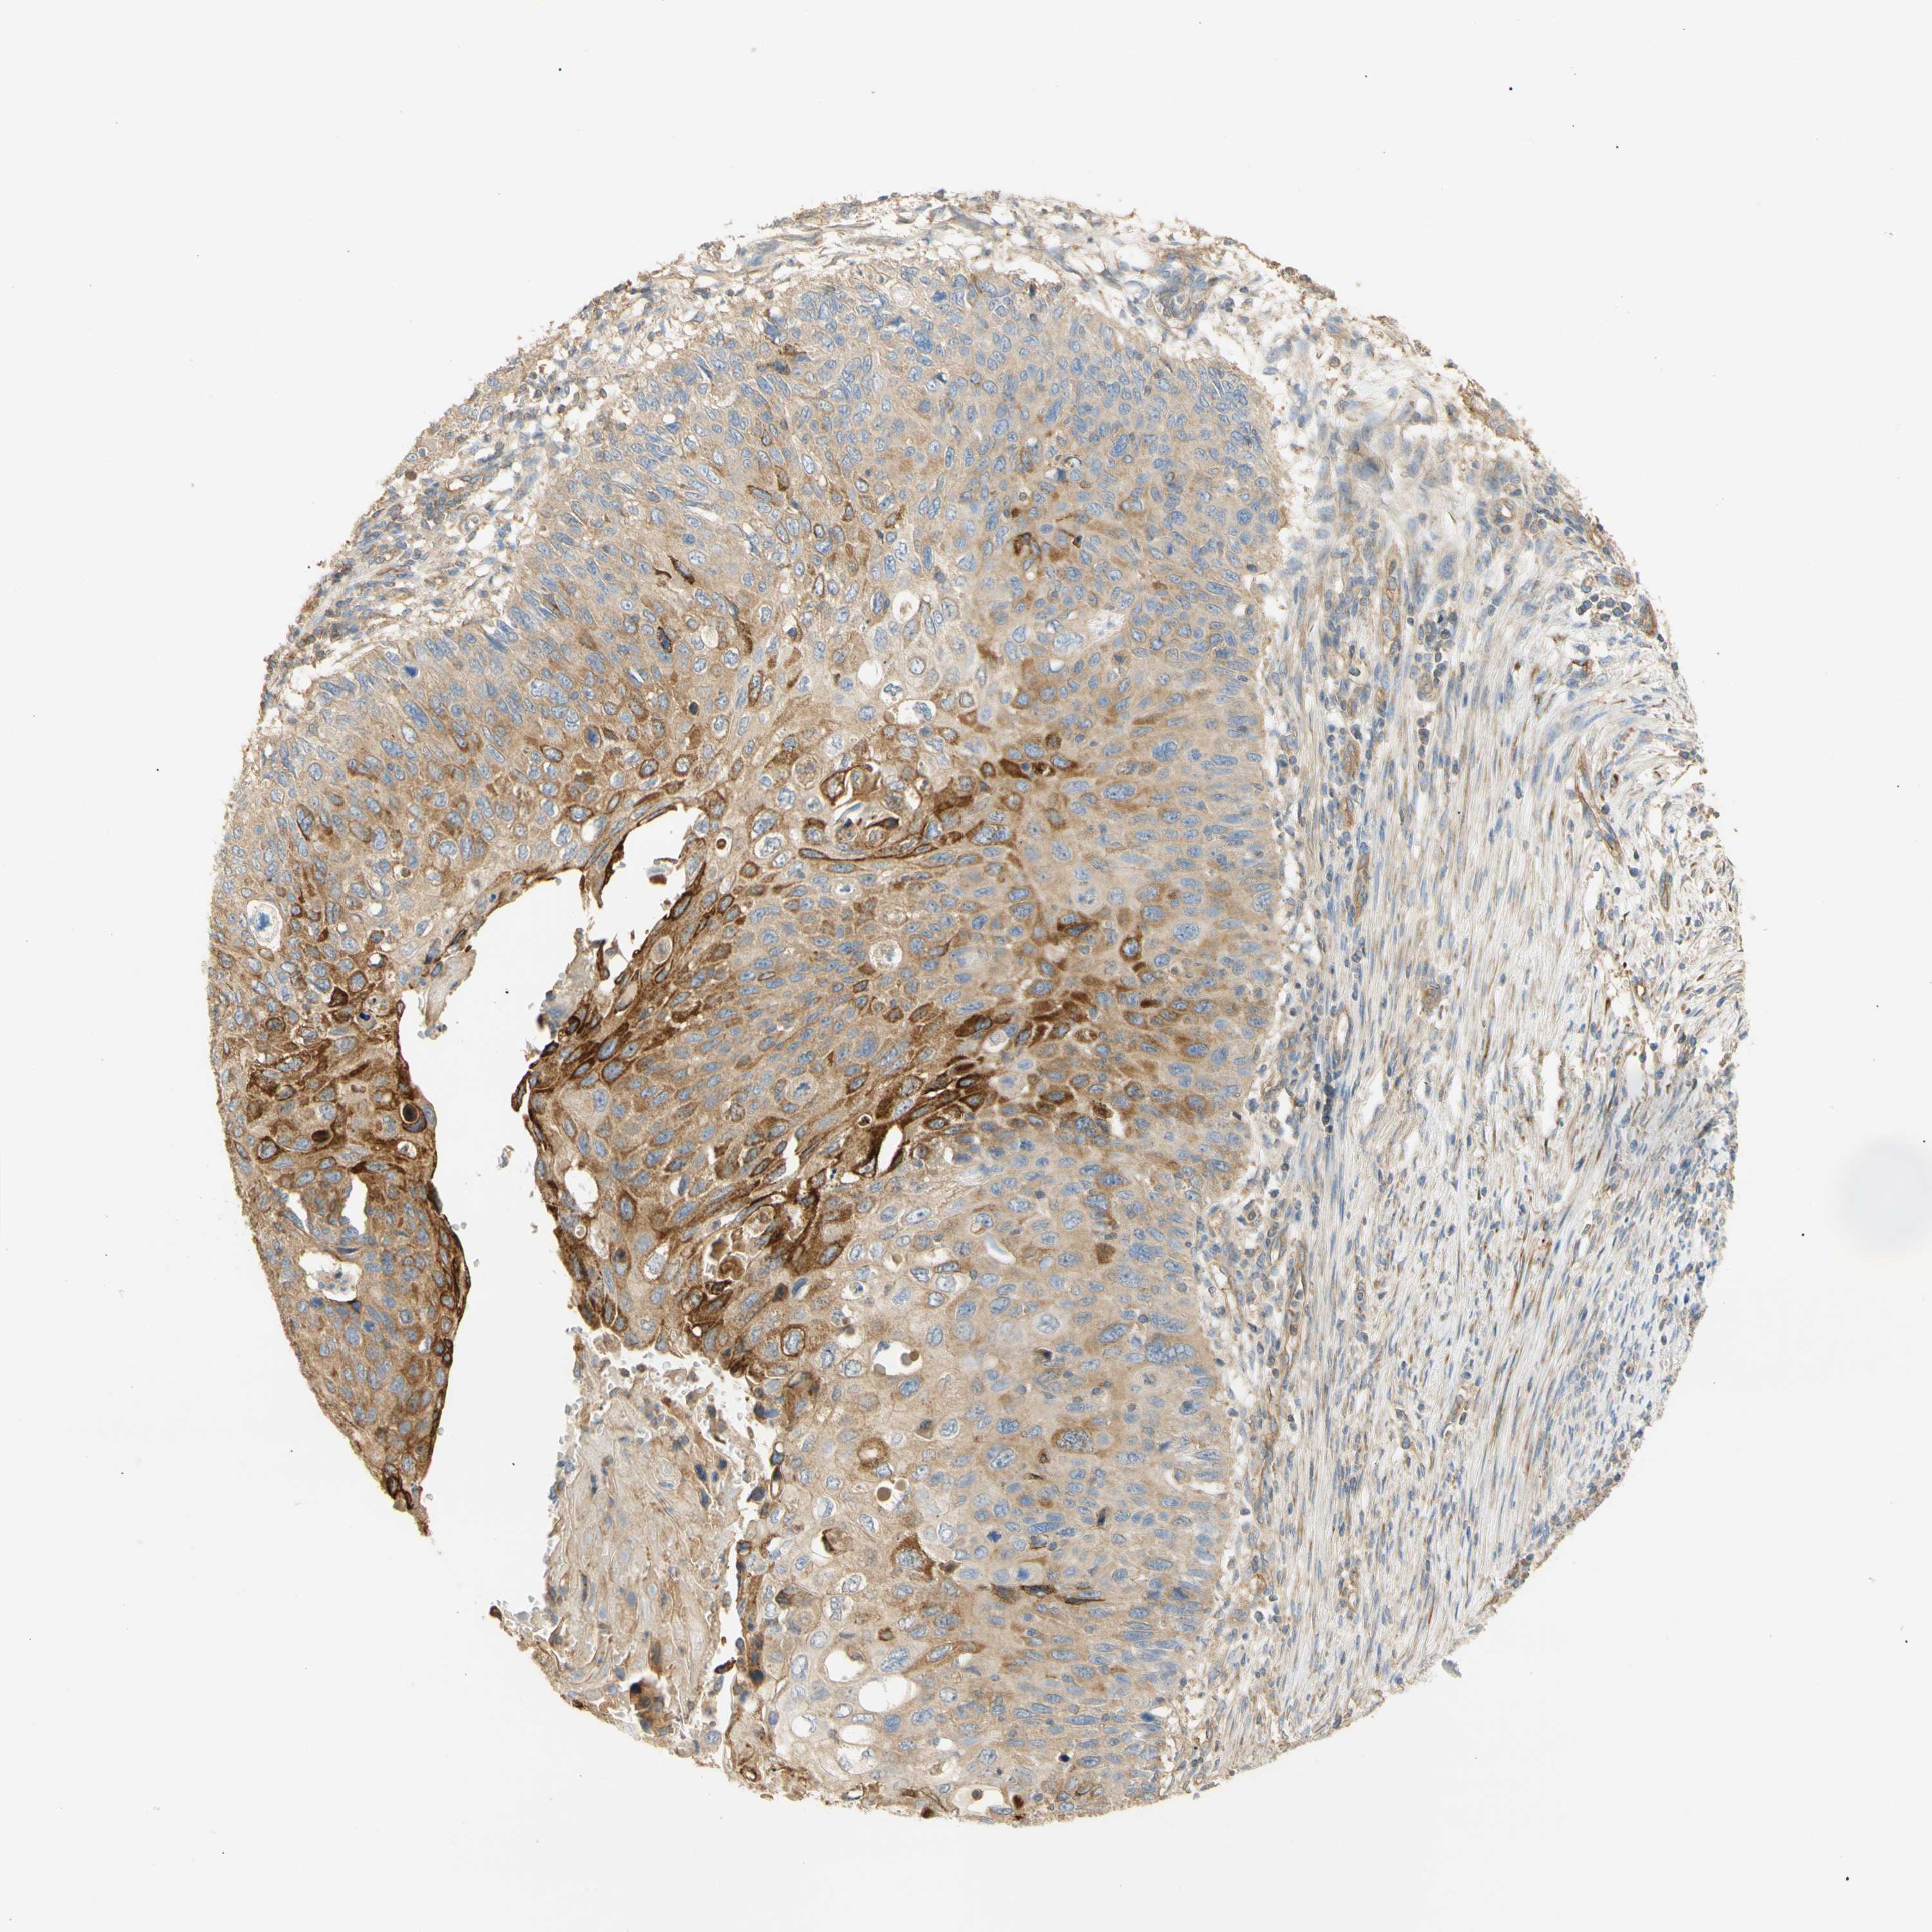

CERVICAL CANCER - Protein expressioni

A mouse-over function shows sample information and annotation data. Click on an image to view it in a full screen mode. Samples can be filtered based on level of antibody staining by selecting one or several of the following categories: high, medium, low and not detected. The assay and annotation is described here.

Note that samples used for immunohistochemistry by the Human Protein Atlas do not correspond to samples in the TCGA dataset.

Antibody stainingi

Antibody staining in the annotated cell types in the current human tissue is reported as not detected, low, medium, or high, based on conventional immunohistochemistry profiling in selected tissues. This score is based on the combination of the staining intensity and fraction of stained cells.

Each image is clickable and will lead to virtual microscopy that enables deeper exploration of all samples and also displays staining intensity scores, fraction scores and subcellular localization as well as patient and tissue information for each sample.

Antibody HPA011420

Staining

High

Medium

Low

Not detected

Intensity

Strong

Moderate

Weak

Negative

Quantity

>75%

75%-25%

<25%

None

Location

Nuclear

Cytoplasmic/membranous

Cytoplasmic/membranous,nuclear

Squamous cell carcinoma, NOS

Adenocarcinoma, NOS